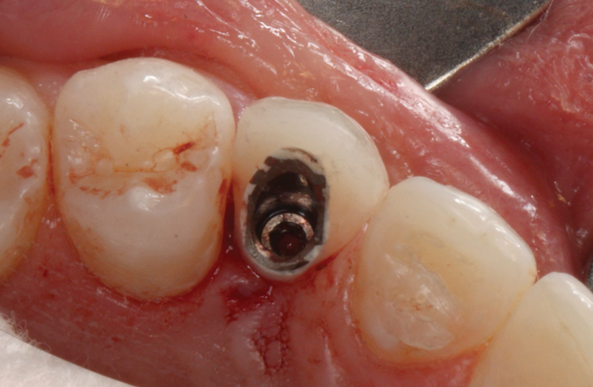

(46.) Occlusal view of the implant after placement.

Figure 46